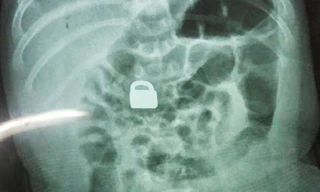

TPO - Cha mẹ của 2 cậu bé ở thành phố Long Nham, tỉnh Phúc Kiến, Trung Quốc đã vô cùng hoảng sợ khi đứa lớn 2 tuổi thừa nhận cho em trai mới 2 tháng tuổi ăn ổ khóa, Mirror đưa tin hôm 4/8.